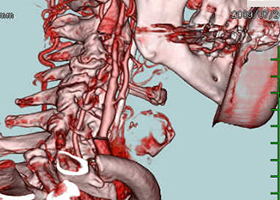

② 頚動脈狭窄症

脳梗塞の原因となる頚動脈狭窄症に対して内膜剥離術を行います。

56歳男性、左半身麻痺で発症しました。

[術前画像所見]

右側で頸部内頚動脈が細くなっているため右脳に脳梗塞を生じた患者様です。